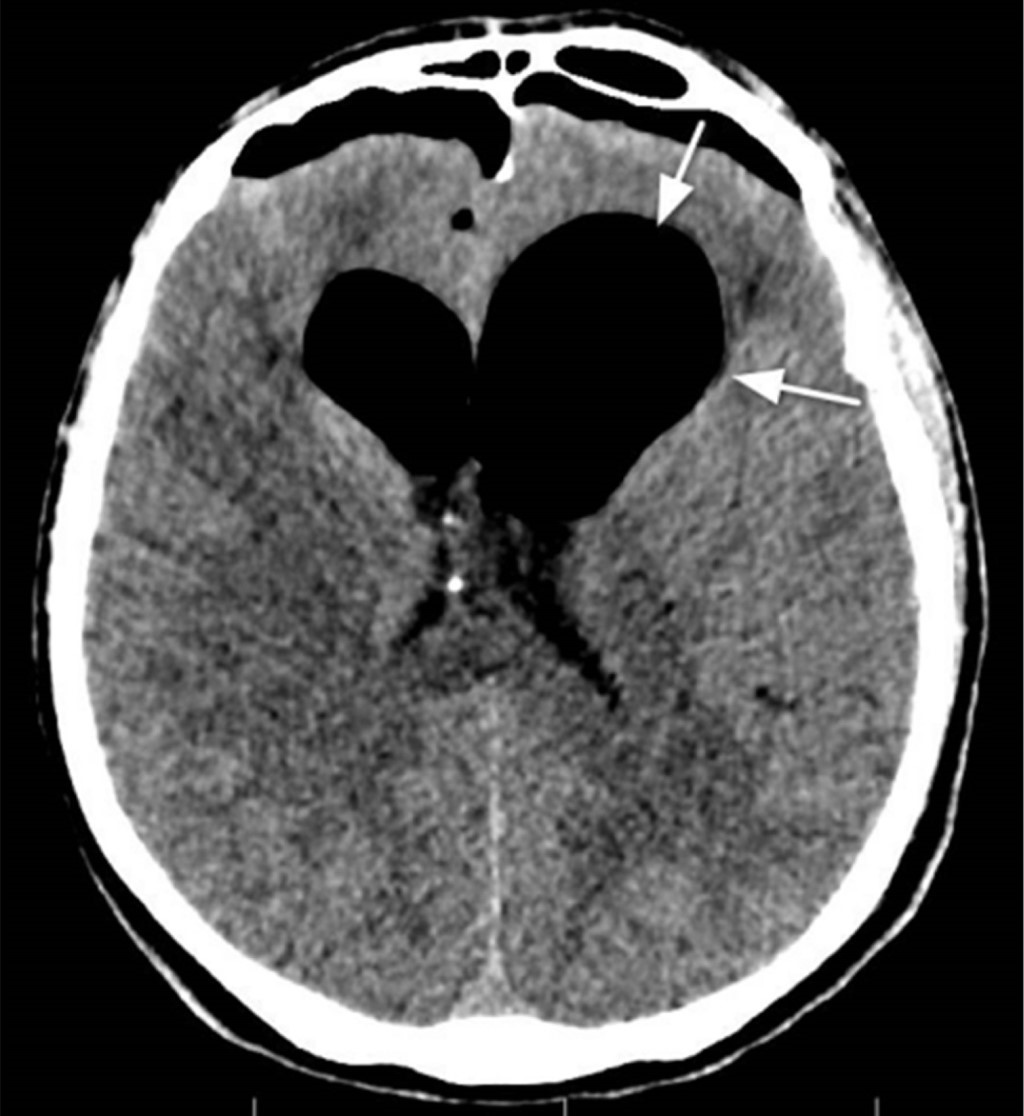

En el tercer día postoperatorio, el paciente presentó vómitos, cefalea, confusión mental y disminución del nivel de conciencia. La tomografía computarizada mostraba edema adyacente al lugar de inserción del tornillo frontal izquierdo, sin alteraciones en el parénquima encefálico o los ventrículos (Figura 3). El examen del líquido cefalorraquídeo mostraba signos sugestivos de proceso infeccioso (aumento de glucosa y proteínas). Se inició antibioticoterapia considerando la hipótesis diagnóstica de meningitis. El paciente mantuvo deterioro del nivel de conciencia. La exploración complementaria con resonancia magnética realizada después de once días mostró neumoencéfalo bilateral en la región frontal y en los ventrículos laterales (Figura 4). Diecisiete días después de la retirada del halo craneal, se realizó una tomografía computarizada que evidenció neumoencéfalo y neumoventrículo con signos de tensión y dilatación de los ventrículos laterales (Figura 5).